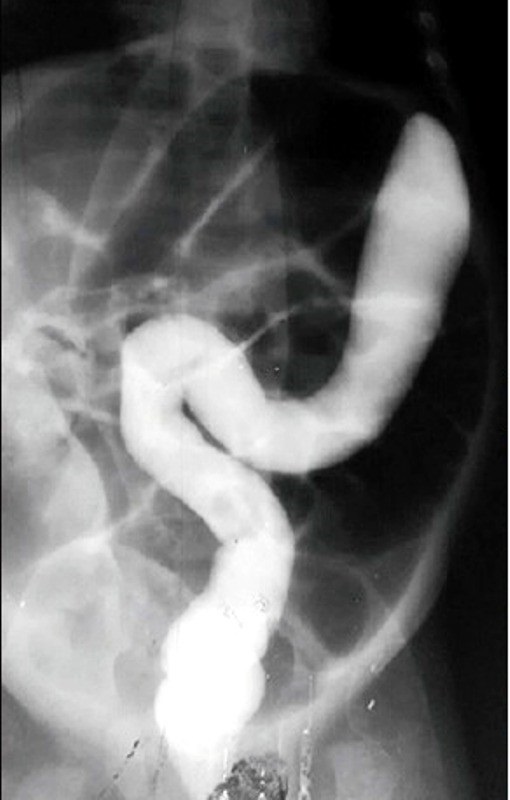

Figure 1

Barium enema showing contrast not traversing beyond the splenic flexure